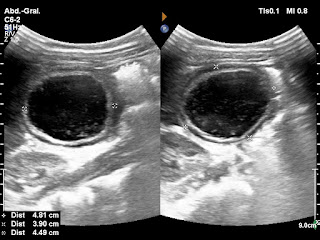

Paciente de 72 años con antecedente de tuberculosis genitourinaria hace 40 años.